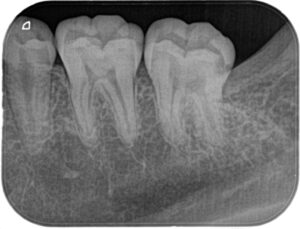

親知らずを抜いた後に小さいX線写真を撮ると第二大臼歯遠心に大きな虫歯がはっきりと写ってきました(下の赤い部分が虫歯です)

一般的には第二大臼歯の咬合面から大きく削り、インレーと呼ばれる詰め物を作ると思います。下の写真のオレンジ色の部分を削るため、虫歯の部分1に対して健康な部分を2~3ぐらい削ります。